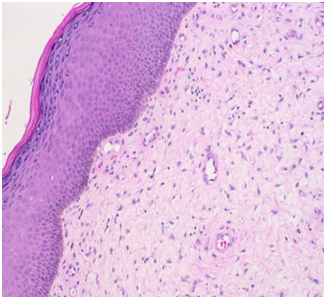

The soft tissue sonogram showed a mass measuring approximately 5.3 cm x 4.7 cm x 2.3 cm, which was projecting from a vascular stalk on the labial majora. The lesion was mildly heterogeneous in echotexture, appearing predominantly solid (Figure 3). The patient underwent wide local excision of the mass. Pathology of the mass showed an aggressive angiomyxoma. The pathologist also noted “this mesenchymal lesion is locally aggressive with a high risk for recurrence if incompletely excised. Although the pedicle margin of resection appears free of the lesional process further clinical concern may warrant conservative excision at the site of lesion attachment”. It was also noted that the mass was hypocellular and composed of stellate cells with an ill-defined cytoplasm distributed through a finely fibrillar and myxoid matrix. The nuclei were bland and mitoses were not present. There were numerous thin and thick walled blood vessels that blended with the surrounding matrix (Figures 5-8).

Figure 5 The overlying epithelium shows mild hyperkeratosis, mild hypergranulosis and mild acanthosis. The tumor lies immediately deep to the epithelium. (H&E Stain).